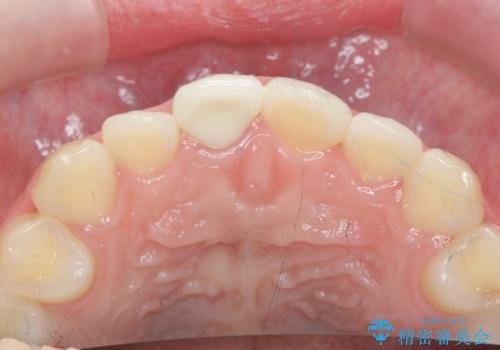

歯ぐきにできものができた 前歯の色調改善

- 歯ぐきに、にきびのようなものができ治らない、と治療を希望され来院されました。

歯髄の検査、X線検査より神経の失活が確認されたので、根管治療・ファイバーコア築盛 ・ジルコニアクラウンの製作、と治療を進めます。

根管治療を行ったことで、歯ぐきのできものは治癒し再発をしなくなりました。